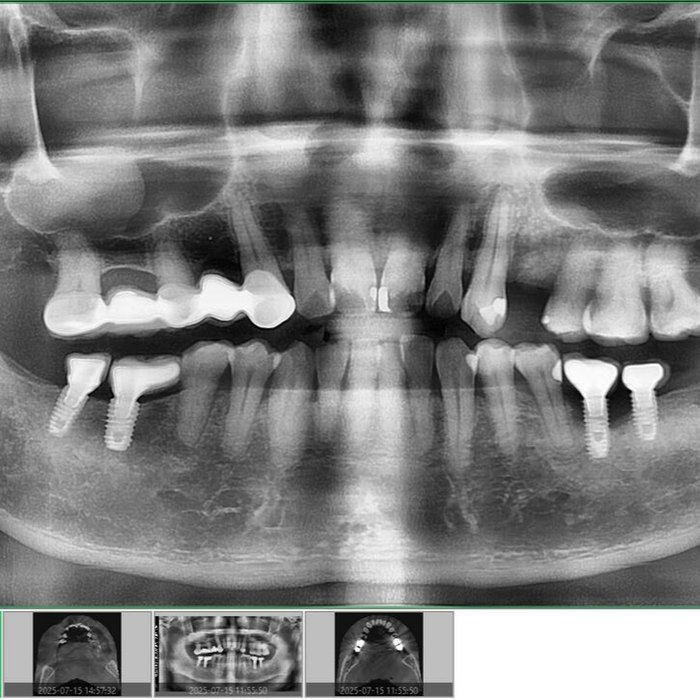

How do you know if I have retained roots?

X-rays or 3D imaging reveal fragments that may not be visible or causing symptoms yet.